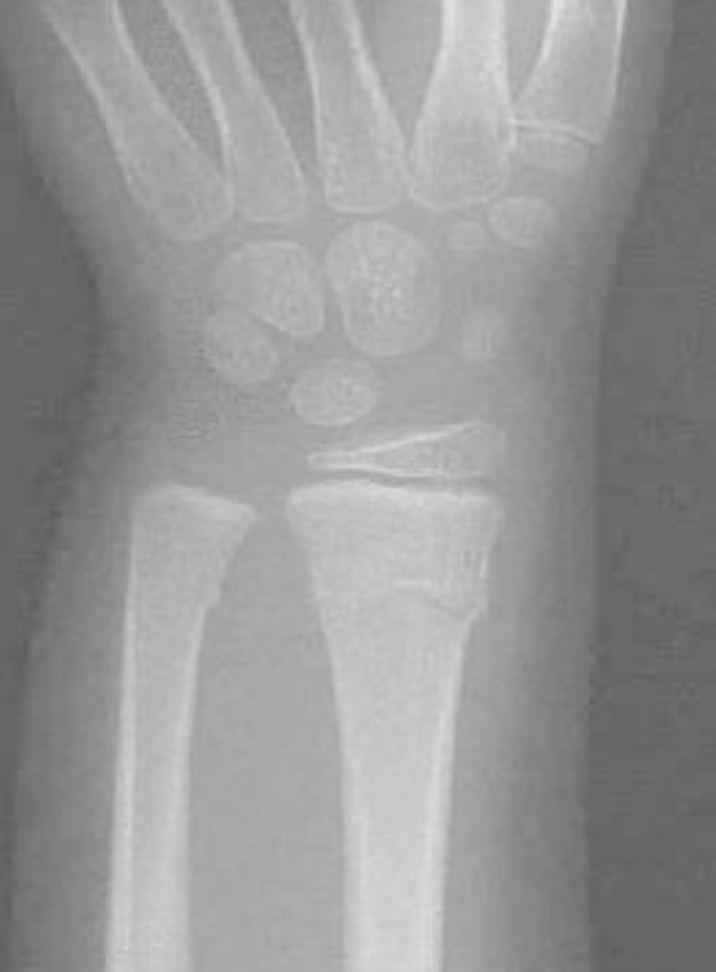

6. Growth Plate Fractures

• Definition: This occurs when the growth plate or physis through the wrist is involved in the injury.

• Special considerations: Most commonly occur at the wrist.  There is a large amount of remodeling potential when fractures occur near or through physis, especially in younger children. But as kids age, growth plate fractures may cause longer-term disfiguration (since there is less room to “grow out” of a deformity”

• Treatment: If displaced: gentle manipulation to get the fracture in place and then short arm cast. Try to limit to one attempt to reduce chance of growth arrest (when the physis is damaged and bone is no longer able to grow